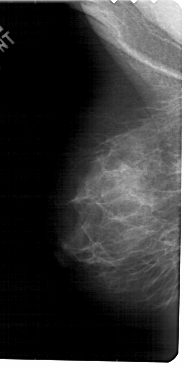

A_1794_1.RIGHT_MLO

RIGHT_MLO LINES 5491 PIXELS_PER_LINE 2671 BITS_PER_PIXEL 12 RESOLUTION 43.5 OVERLAY